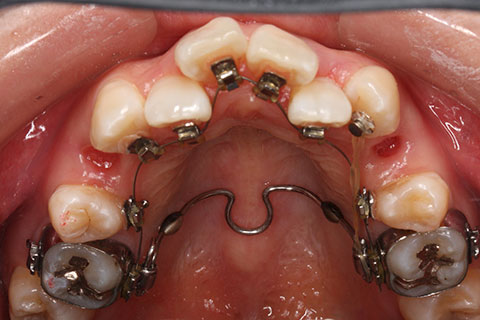

治療前

治療中(開始直後)

治療中(開始半年後)

治療後

- 年齢・性別

- 25歳女性

- 治療期間

- 2年0ヶ月

- 抜歯

- 上下4番抜歯

- 治療費

- 110万円

- 治療内容

- 施術の副作用(リスク)

- 表側矯正と比較して、力学的な操作性が複雑なため、ボーイングエフェクトを起こしやすい。